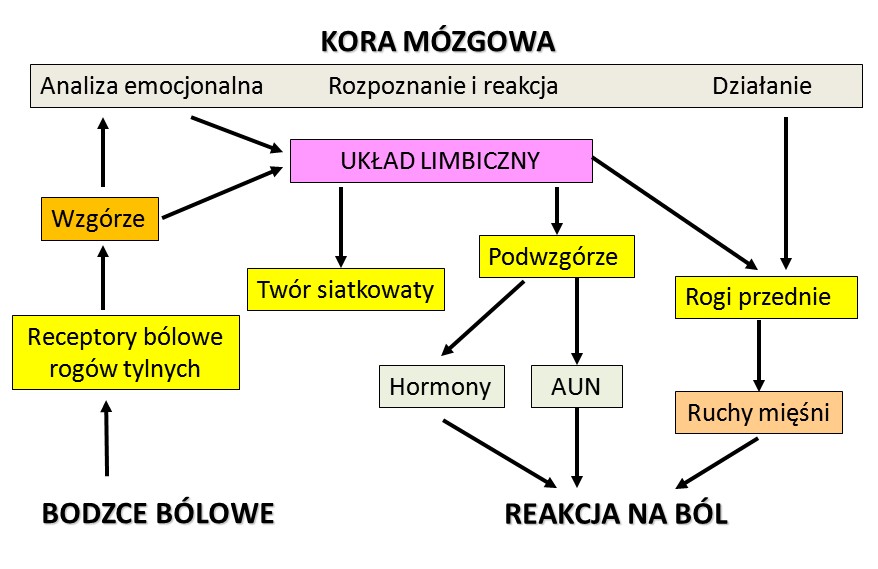

Uproszczony schemat dróg reakcji na ból.